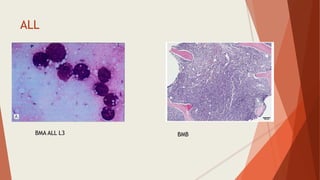

ALL

BMA ALL L3 BMB